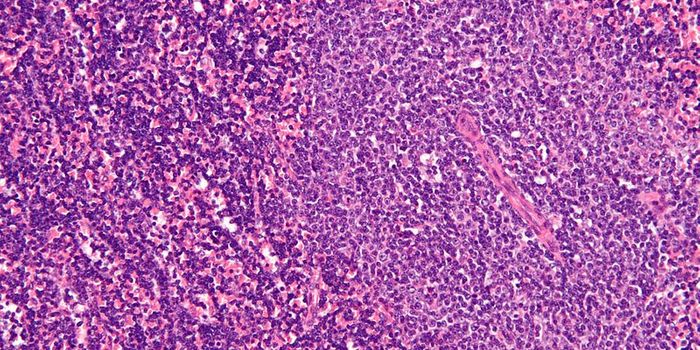

MAR 18, 2015Immunology

After a chance observation in the lab, researchers found a method that can force dangerous leukemia cells in the l ... -